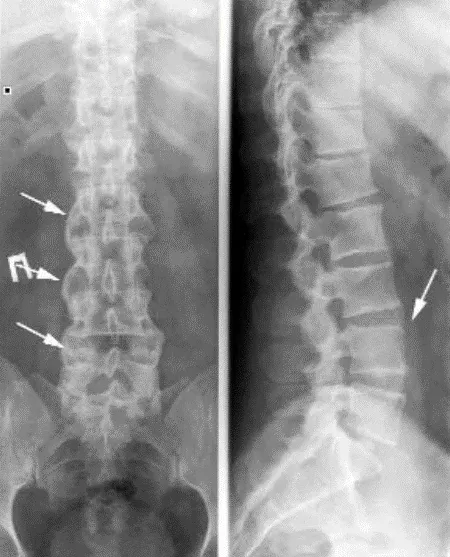

Аксиальное поражение при ПсА имеет ряд особенностей. В 25% случаев сакроилиит и спондилит при ПсА протекают латентно (без боли). Сакроилиит при ПсА, в отличие от АС, – часто асимметричный. Для ПсА характерно медленное рентгенологическое прогрессирование сакроилиита, полный анкилоз КПС на фоне длительного течения заболевания отмечается значительно реже, чем при АС (до 6% пациентов). При ПсА возможно поражение позвоночника (рентгенологические признаки спондилита) без сакроилиита, чего не наблюдается при анкилозирующем спондилите (АС). При ПсА, в противоположность АС, синдесмофиты чаще малочисленны, расположены асимметрично, в случайном порядке, не вдоль ≪последовательно идущих≫ позвонков, имеют больший размер и объемную форму, встречаются паравертебральные синдесмофиты (ПВС) – особый вариант обызвествления передней продольной связки позвоночника. ПВС представляют собой широкие грубые оссификаты, которые отстоят от края тела позвонка. Также наблюдаются краевые синдесмофиты (КС) – вертебральные оссификаты, отходящие от края тела позвонка вверх. КС могут образовывать ≪мостики≫ между позвонками. КС и ПВС ориентированы вверх (сужения смежного межпозвонкового промежутка не наблюдается). Это отличает их от выявляемых при дегенеративных заболеваниях позвоночника остеофитов (или спондилофитов), которые ориентированы горизонтально, около измененного диска (сужение межпозвонкового промежутка). Нередко, несмотря на существенные рентгенологические изменения, у больных отсутствуют заметные функциональные нарушения, что также отличает спондилит при ПсА от поражения позвоночника при АС. Спондилит и сакроилиит могут наблюдаться при любой клинической форме ПсА.

Рисунок 11. Рентгенограммы нижнегрудного и поясничного отделов позвоночника при псориатическом артрите. Спондилит, грубые синдесмофиты, уплотнение передней продольной связки (стрелки)